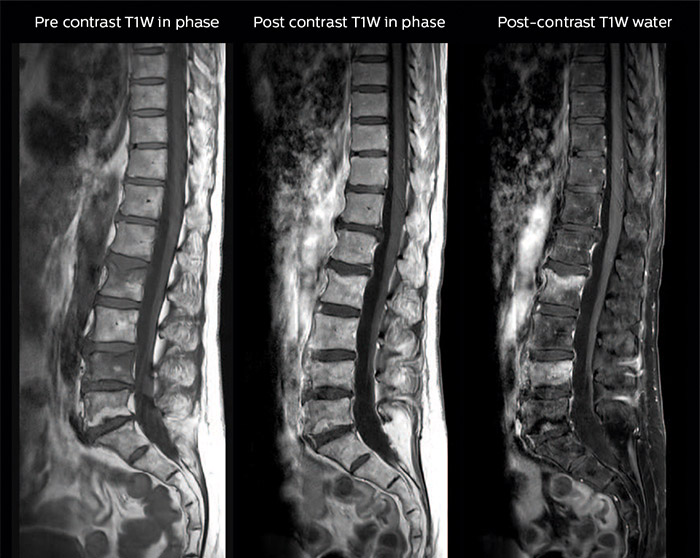

Spine scans must be fast and complete

“In our spine cases, we use mDIXON TSE for patients with degenerative and inflammatory spine issues, vertebral fractures and vertebral and paravertebral tumor characterization,” says Dr. Lefebvre. “It provides, in a single acquisition, different contrasts so we can both visualize and characterize spinal, focal or diffuse spine lesions.”

“mDIXON TSE makes real a difference in cases of acute and traumatic spinal injuries, where it allows us to reduce the scan time by only using a limited number of sequences. For patients in pain, who come from the emergency unit and need surgery, for example, MRI must be very fast. With a single T2-weighted acquisition we can assess spinal cord, vertebral disc and ligament wholeness with in-phase images, as well as trabecular fracture and edematous changes with water images.”

Dr. Lefebvre cites other frequent examples of spinal diseases that benefit from the mDIXON technique. “In cases of vertebral disc herniation or degenerative discs, for example, we don’t have to choose between fat or no fat images. We can assess morphological changes in the endplate with in-phase images from T2-weighted sequences and in the water image from the same acquisition we will see inflammatory changes into endplates.”

“We can both visualize and characterize spinal, focal or diffuse spine lesions.”